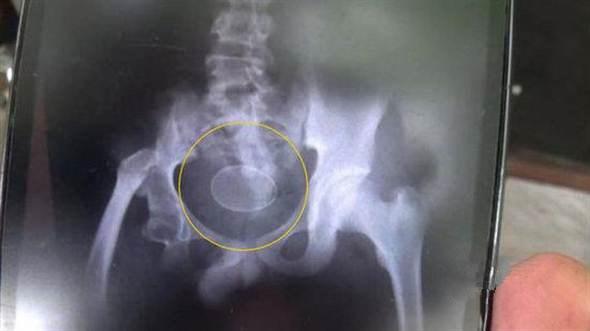

Sau khi chụp X- quang, các bác sĩ đã hết sức bối rối khi nhìn thấy một vật thể có hình dạng và kích thước tương tự như một quả trứng ở vùng chậu của cậu bé.

Phim chụp X- quang hiện lên vật thể lạ giống trứng.